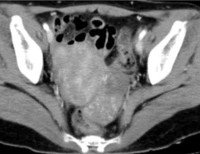

• Интроскопические методы. Основным методом инструментальной диагностики является УЗИ органов малого таза, которое позволяет обнаружить даже небольшие образования и предположить наличие опухоли Бреннера по характерным ультразвуковым признакам. Для уточнения диагноза также могут быть назначены КТ и МРТ таза.